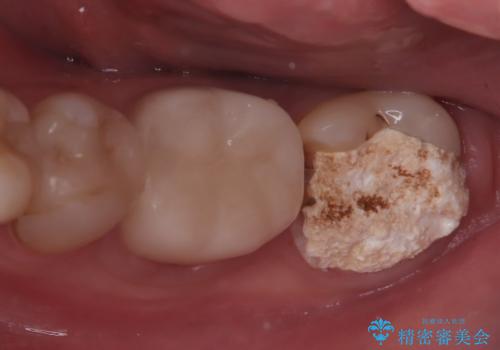

【根管治療】他院でインプラントの提案があった。奥歯が痛い。

- 左下の奥歯の治療の継続を主訴に来院されました。

1週間ほど前に、自発痛の既往があり他院で応急処置を行ってもらったとのことです。

そこでは、抜歯してインプラントの治療を提案されたとのことです。

レントゲンや口腔内所見にて以下のような説明ののち、患者様が保存を希望されたため、当院では根管治療~オールセラミッククラウンにて修復処置を行いました。痛みも消えて、経過良好です。